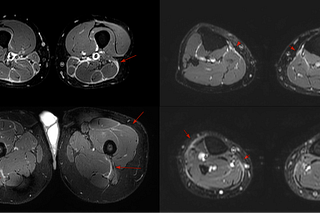

Case 61: Dermatomyositis and the Myositis Protocol MRI

55-years old with dermatomyositis